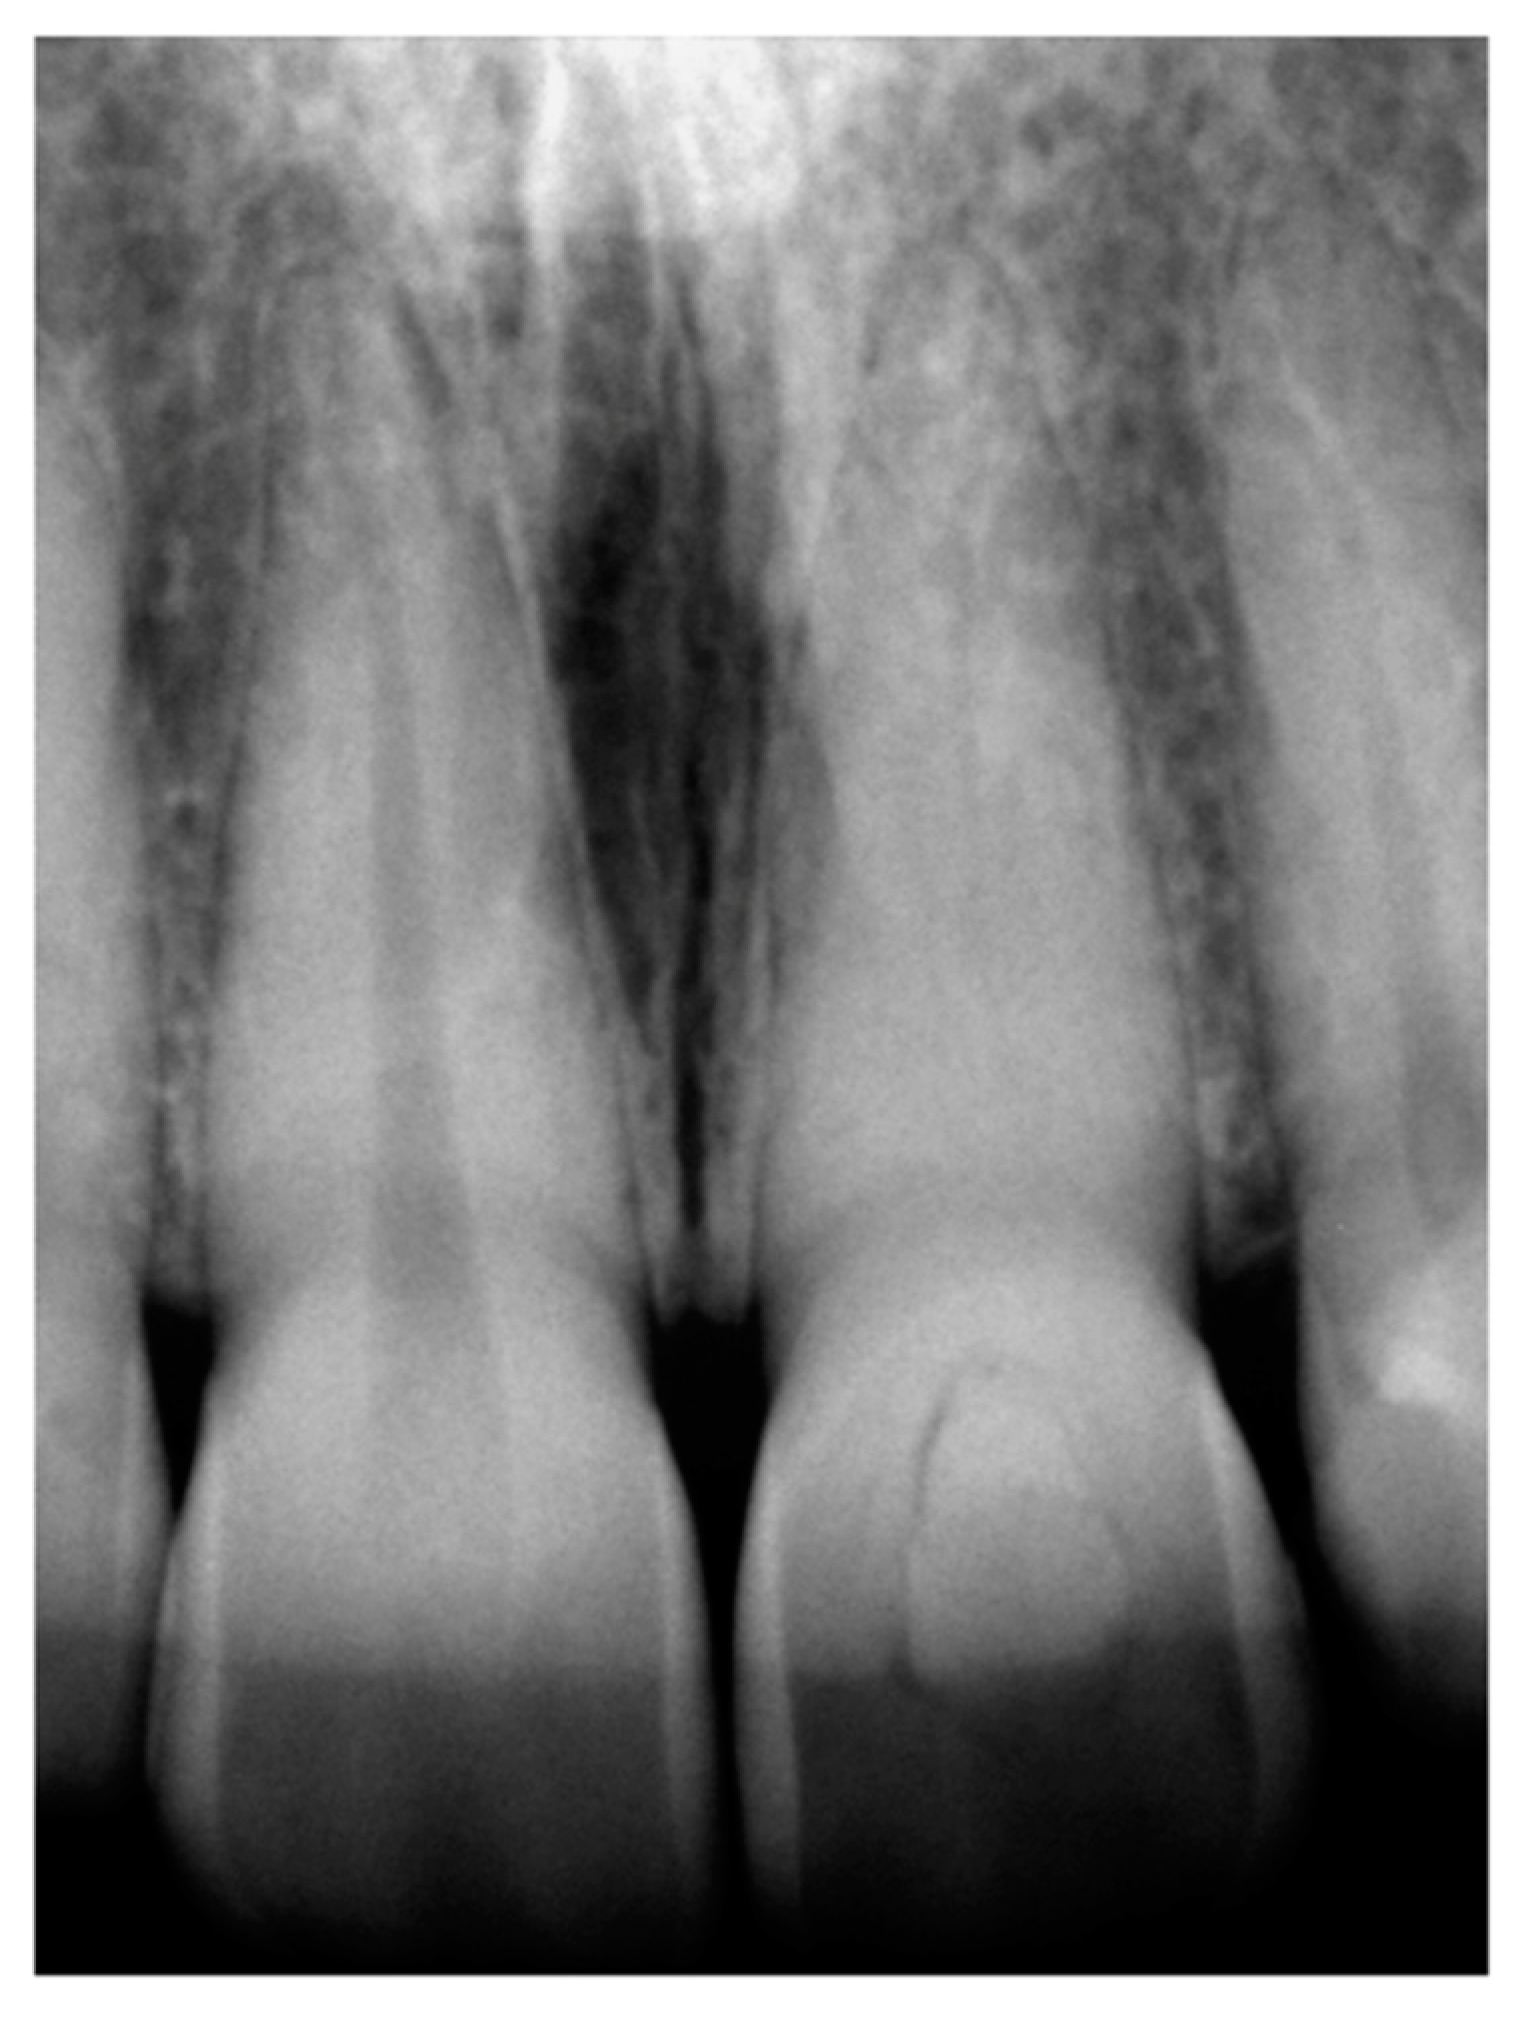

2. Case Presentation